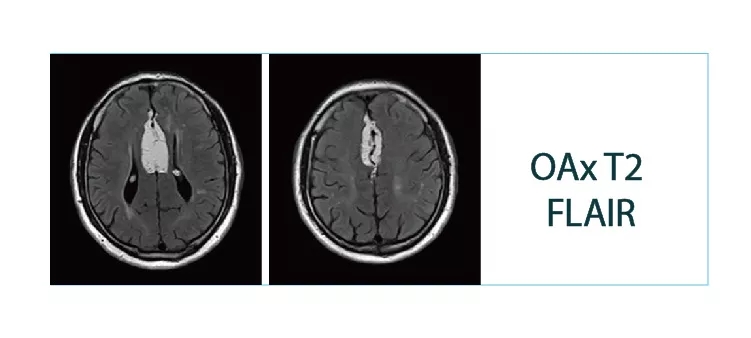

【朗润影像档案】20180511磁共振影像病例结果讨论